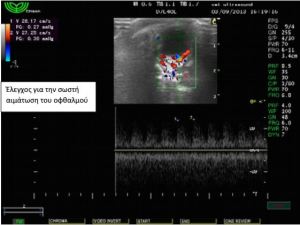

Έγινε υπέρηχος όπου διαπιστώθηκε συγκέντρωση υγρού

αυξημένης ηχογένειας στη περιοχή πίσω από το δεξιό οφθαλμό,

εικόνα συμβατή με οπισθοβολβικό απόστημα. Η αλλοίωση